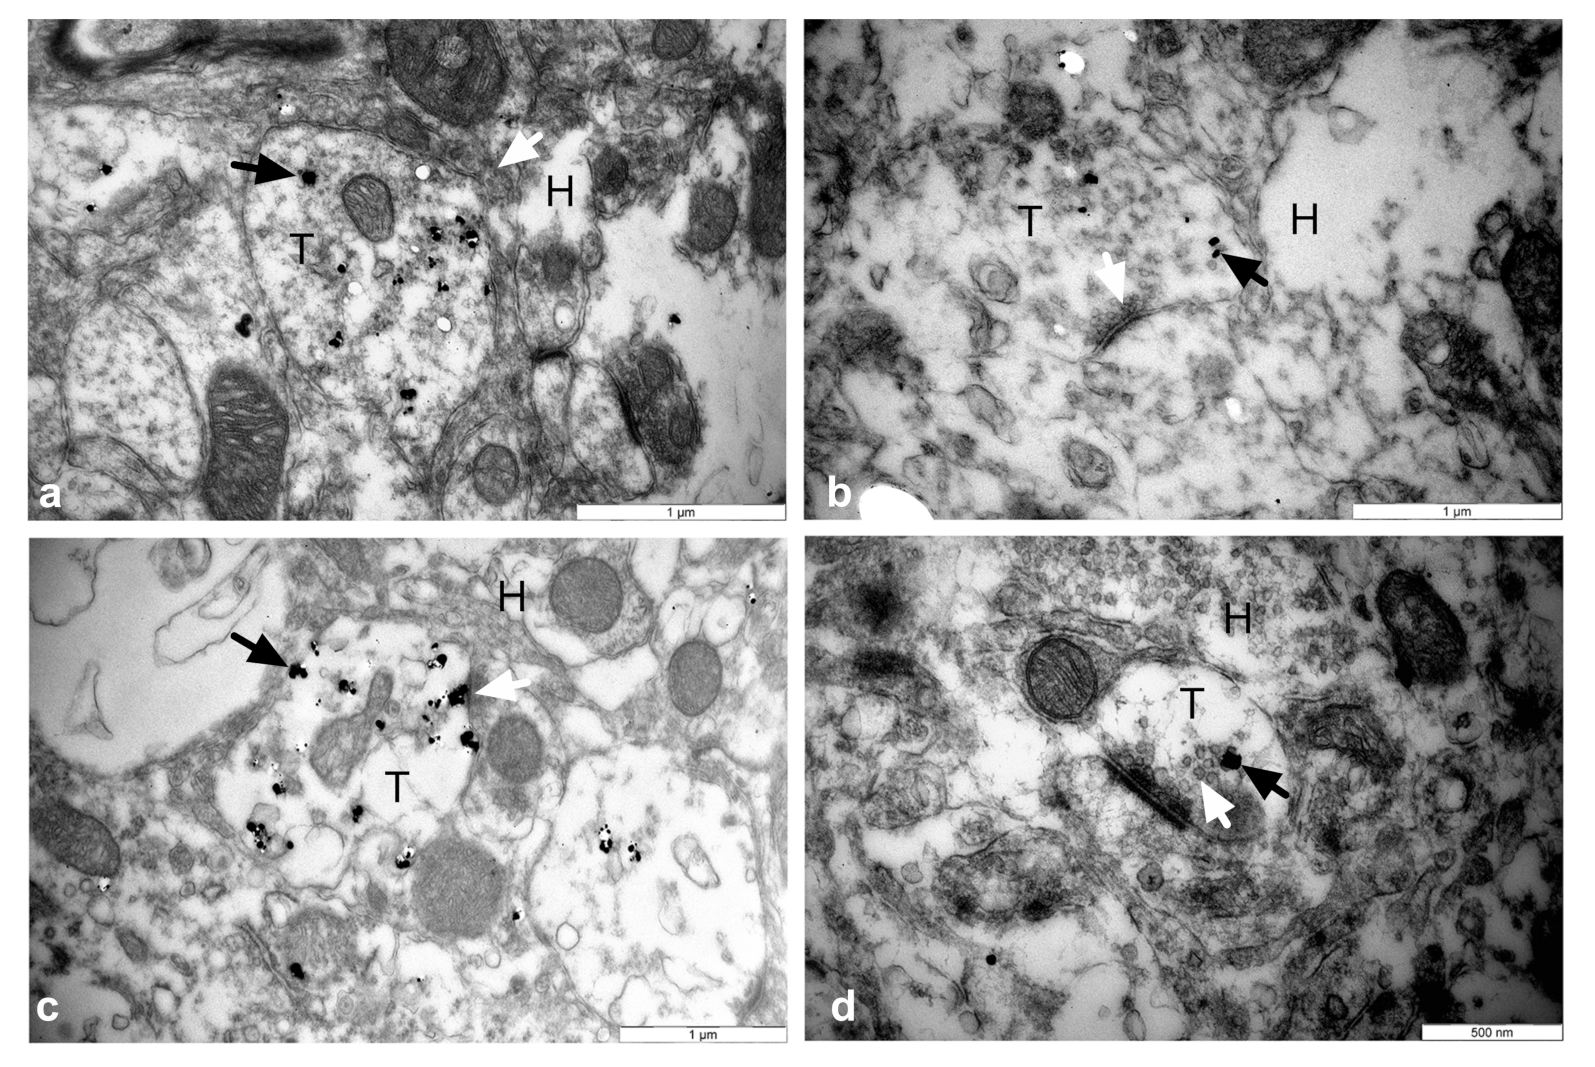

3.5. Establishment of Reciprocal Synaptic Contacts between Intrastriatal or Intranigral Transplants and Host Neurons

| Functional comparison | Synaptic contacts | Establish reciprocal synaptic contacts with the host circuits | ||